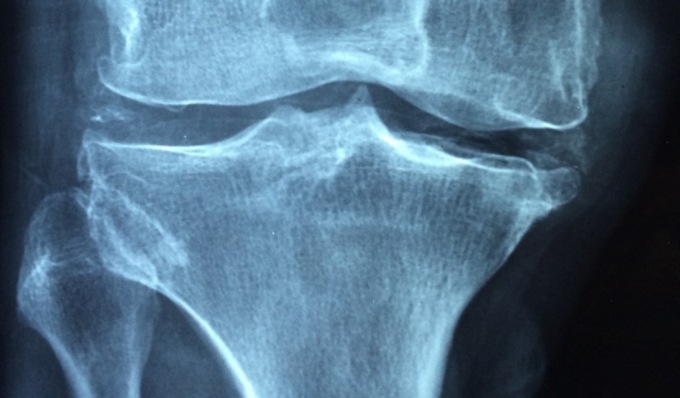

Una malattia che compromette la salute delle ossa e che spesso passa inosservata

L’incontro, fissato per le ore 10.45 presso il Palazzo del Broletto, avrà come obiettivo principale quello di sensibilizzare i partecipanti sull’importanza della conoscenza e del riconoscimento dell’osteoporosi, una malattia che compromette la salute delle ossa e che spesso passa inosservata.

“L’osteoporosi è una condizione fisiopatologica correlata epidemiologicamente alla menopausa e all’invecchiamento, ma può colpire anche giovani donne e uomini, renderli inaspettatamente e precocemente fragili e gravare così sulla loro quotidianità e su quella dei lori cari.

La frattura da fragilità, che insorge su un osso osteoporotico, non è quindi un evento isolato, da gestire in acuto e dimenticare, bensì espressione e parte di una patologia cronica, silente, non visibile, nonché fattore di rischio per nuove fratture da fragilità. In questo contesto, la presa in carico del paziente con osteoporosi o frattura da fragilità, e il suo inserimento in un corretto iter diagnostico-terapeutico, dovrebbe essere un punto cardine della gestione di malattia che coinvolge diverse figure professionali a differenti livelli e dove la multidisciplinarietà e multiprofessionalità rappresentano un valore aggiunto alla base di una costante crescita.

La frattura da fragilità, l’aspetto più evidente della malattia da fragilità ossea, così come l’osteoporosi, viene troppo spesso considerata espressione dell’ineluttabile invecchiamento dell’individuo, evento fisiologico della donna in menopausa e dell’anziano, e non una patologia cronica e severa gravata da un’elevata disabilità e mortalità se non correttamente trattata”.